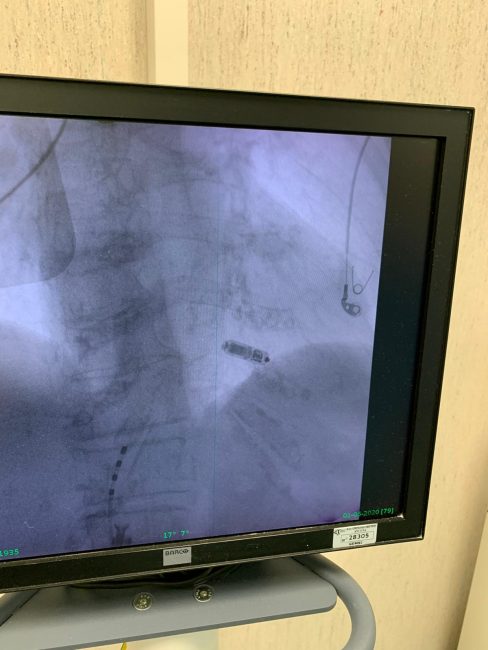

Un momento dell’operazione

«Le Marche – spiega il direttore generale Michele Caporossi – annoverano oggi tra le alte specializzazioni anche l’elettrofisiologia, che sempre di più dà risposte efficaci a pazienti complessi per i quali è sempre stata alta la propensione ai viaggi della speranza, specialmente verso il nord Italia. Oggi di questo non c’è più bisogno. Qui abbiamo di tutto e di più». Il blocco AV è una tipologia di blocco cardiaco in cui risultano compromessi i segnali elettrici tra le camere del cuore (gli atri e i ventricoli). Il pacemaker, ossia il più comune strumento per trattare i blocchi AV, ripristina il normale ritmo cardiaco. Storicamente il tradizionale pacemaker è impiantato sottopelle in regione pettorale e collegato al cuore grazie a dei fili chiamati “elettrocateteri”. Comparabile in dimensioni ad una compressa di vitamine, il prof Dello Russo ha scelto di utilizzare il dispositivo Medtronic Micra AV per la capacità di erogare terapia con un approccio mininvasivo. E’ una sorta di pacemaker invisibile, il Micra AV, che viene inserito dall’inguine del paziente e fissato con delle piccole ancore al cuore. Dal momento che il Micra AV non richiede elettrocateteri o la creazione di una “tasca” chirurgica sottopelle, le possibili complicanze relative a tasca ed elettrocateteri sono del tutto eliminate, così come qualsiasi traccia visibile del dispositivo stesso.

Il mini pacemaker impiantato